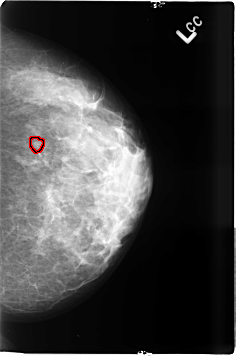

B_3497_1.LEFT_CC

LEFT_CC LINES 4624 PIXELS_PER_LINE 3056 BITS_PER_PIXEL 12 RESOLUTION 50 OVERLAY

FILE: B_3497_1.LEFT_CC.OVERLAY

TOTAL_ABNORMALITIES 1

ABNORMALITY 1

LESION_TYPE CALCIFICATION TYPE PLEOMORPHIC-AMORPHOUS DISTRIBUTION

CLUSTERED

ASSESSMENT 4

SUBTLETY 3

PATHOLOGY BENIGN

TOTAL_OUTLINES 1

BOUNDARY